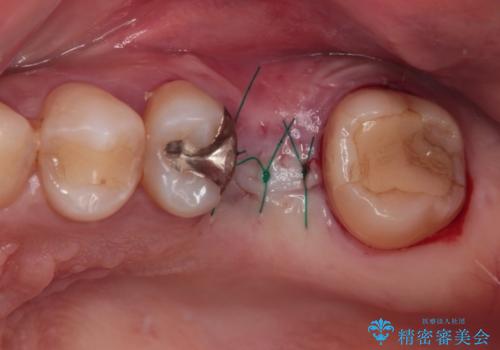

インプラント治療をきっかけに、銀歯を全てセラミックに替えていきました。

人の目を気にせずに、大きく口を開けて笑えるようになりました。